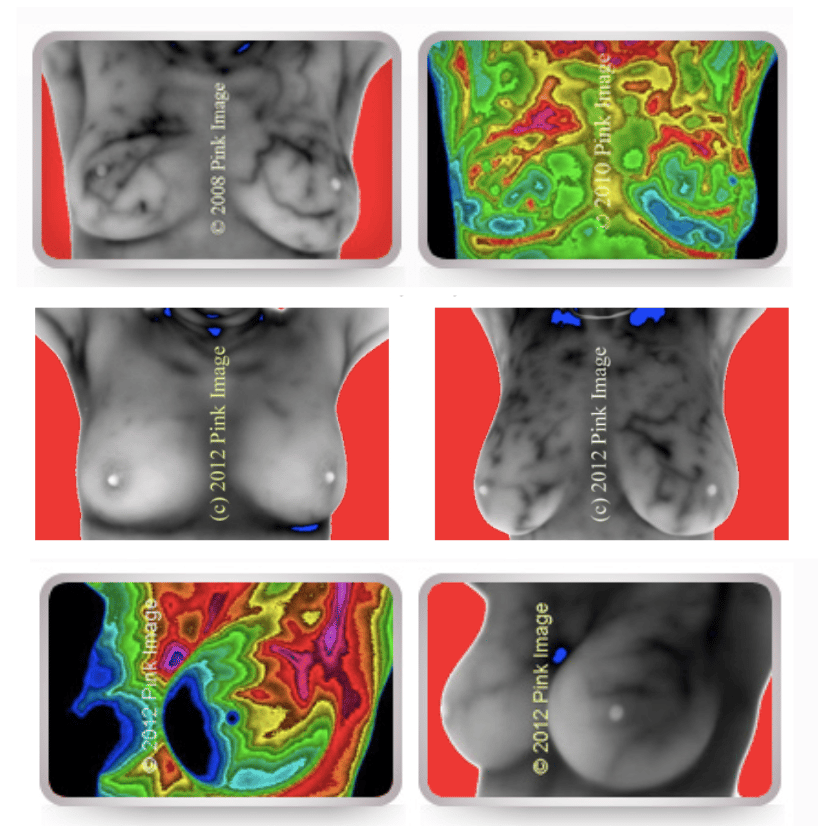

Thermograms use infrared technology to detect heat patterns and changes in blood flow within the breast. Increased vascularity can signal inflammation or abnormal tissue growth, such as the formation of new blood vessels that support a tumor's nutrient supply.

Pros:

Non-invasive and radiation-free.

Comfortable. Since there’s no compression involved, it’s a pain-free option.

Capable of detecting inflammation, which can indicate early-stage changes before a tumor forms.

Cons:

Does not provide a clear picture of the breast.

Small, deep-seated tumors may not cause enough temperature variation to be detected.